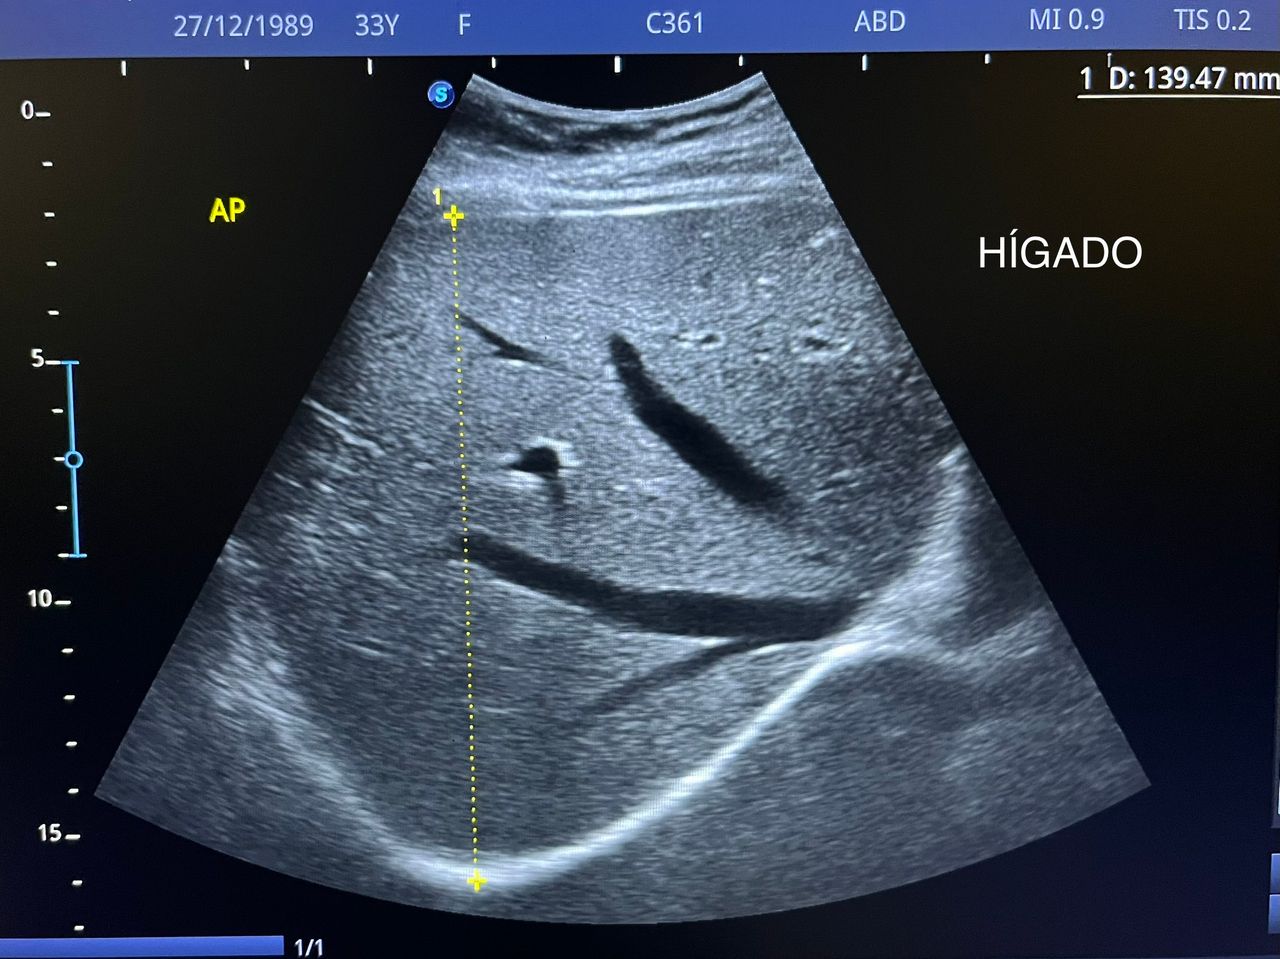

Médico general con 15 años de experiencia, master en enfermedades infecciosas y antibioticoterapia por parte de la Universidad Cardenal Herrera en Valencia, ademas de diversos diplomados en el área de Infectología y Parasitología, Urgencias, Imagenología y Medicina del Trabajo. He laborado en Hospitales y Clínicas en el área de Urgencias, en Laboratorios realizando estudios de Imagen, en especifico ultrasonidos de todo tipo desde básicos hasta avanzados incluidos los obstétricos estructurales, en Secretaría de Salud del Estado de Querétaro realizando ultrasonidos obstétricos para la detección de malformaciones en los tres trimestres del embarazo en diversos centros de salud, como médico de Empresas en el campo de Salud Laboral y actualmente en este consultorio en donde para su mejor atención y siempre buscando integrar la mayoría de las herramientas diagnosticas cuento con equipo de ultrasonido como apoyo en la exploración del paciente o como servicio diagnostico por imagen, realizo ultrasonidos convencionales (hepatobiliar (hígado, páncreas, vesícula y bazo), vías urinarias, ginecológico abdominal y transvaginal, tiroideo, prostático, testicular, pared abdominal) y especializados (dopler obstétrico en los 3 trimestres de embarazo), musculoesquelético en lesiones deportivas. También cuento con un equipo de electrocardiograma de 12 derivaciones para monitoreo completo del funcionamiento cardiaco, espirometria para evaluar la función pulmonar en la consulta, pruebas rápidas que se realizan en consultorio para detectar de forma mas precisa enfermedades infecciosas como Influenza A y B, covid19, infecciones urinarias, dengue, zika, chikungunya. Cuento con diversas vacunas para prevención de enfermedades. Siempre con el objetivo de dar el mejor servicio y atención a su salud. Lo espero en consulta para escucharlo y estudiar su caso de la forma más completa posible, estoy seguro de que tendremos las mejores opciones para su tratamiento. Mi tranquilidad es que usted se vaya con todas sus preguntas e inquietudes resueltas.

• Ultrasonido hepatobiliar

$800